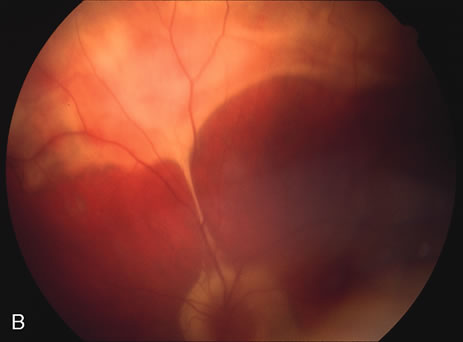

Fundus Findings.

Classically, there are broad areas of chorioretinal atrophy that may take a jigsaw pattern. Usually the atrophy is centered on the disc and spreads along the vascular arcades and then towards the fovea. Sometimes the choroiditis starts within the macula and spreads out from there. Both eyes tend to be affected although there may be marked asymmetry between the two eyes. The active disease appears as yellow-gray areas. If there is evidence of previous disease, then the active areas tend to be at the edge of the chorioretinal atrophy (Figs. 16 to 18). Rarely, there may be several noncontiguous areas of chorioretinal atrophy in the eyes. Retinal vasculitis at the site of an active lesion and retinal vein occlusions may rarely be seen.

Fig. 16. A. Color fundus photograph showing the jigsaw pattern of choroidal and retinal atrophy extending from the disc along the arcades. At the inferior edge of the superotemporal lesion there is a recurrence noted by the grayness of the retina. B. Fluorescein angiogram in the laminar venous phase showing a large window defect in the area of inactive choroiditis and blockage of the choroidal fluorescence in the area of active choroiditis. C. In the late phase of the fluorescein angiogram there is staining of the edges of the inactive choroiditis and marked hyperfluorescence in the area of active choroiditis.

Fig. 17. A. Classic inactive case of serpiginous choroiditis showing the jigsaw pattern of disease surrounding the fovea. B. Fluorescein angiogram showing staining of the edges of the inactive serpiginous choroiditis. There is blocked fluorescence in the areas of hyperplasia of the retinal pigment epithelium. C. Indocyanine green angiogram showing absence of fluorescence in the area of inactive choroiditis.

Fig. 18. Fundus photograph of active macular serpiginous. Because there is no previous evidence of scarring, it is difficult to distinguish by ophthalmoscopy alone from acute posterior multifocal placoid pigment epitheliopathy (APMPPE). The larger size and the age of the patient tend to help in distinguishing.